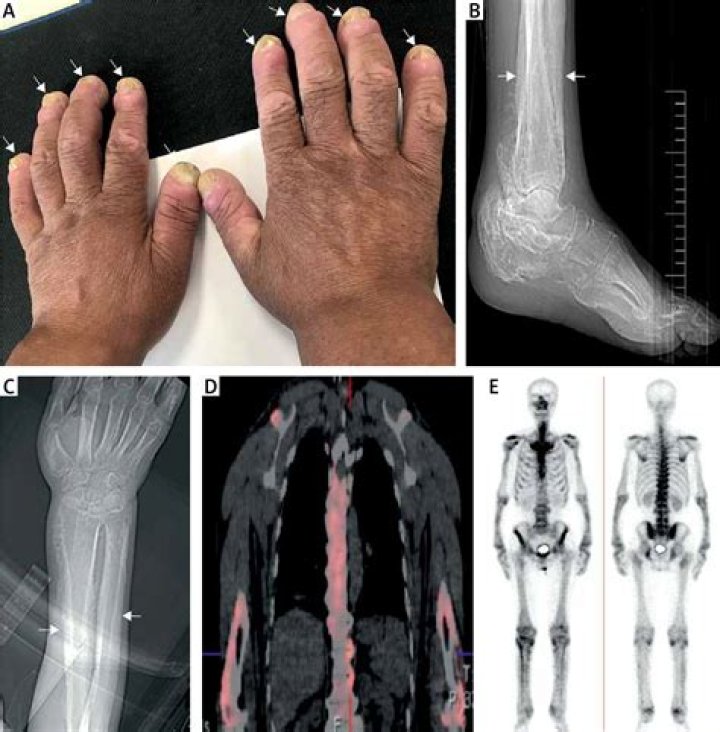

Hypertrophic osteoarthropathy (HOA) is mainly caused by mainly fibrovascular proliferation. It is characterized by a combination of clinical findings,